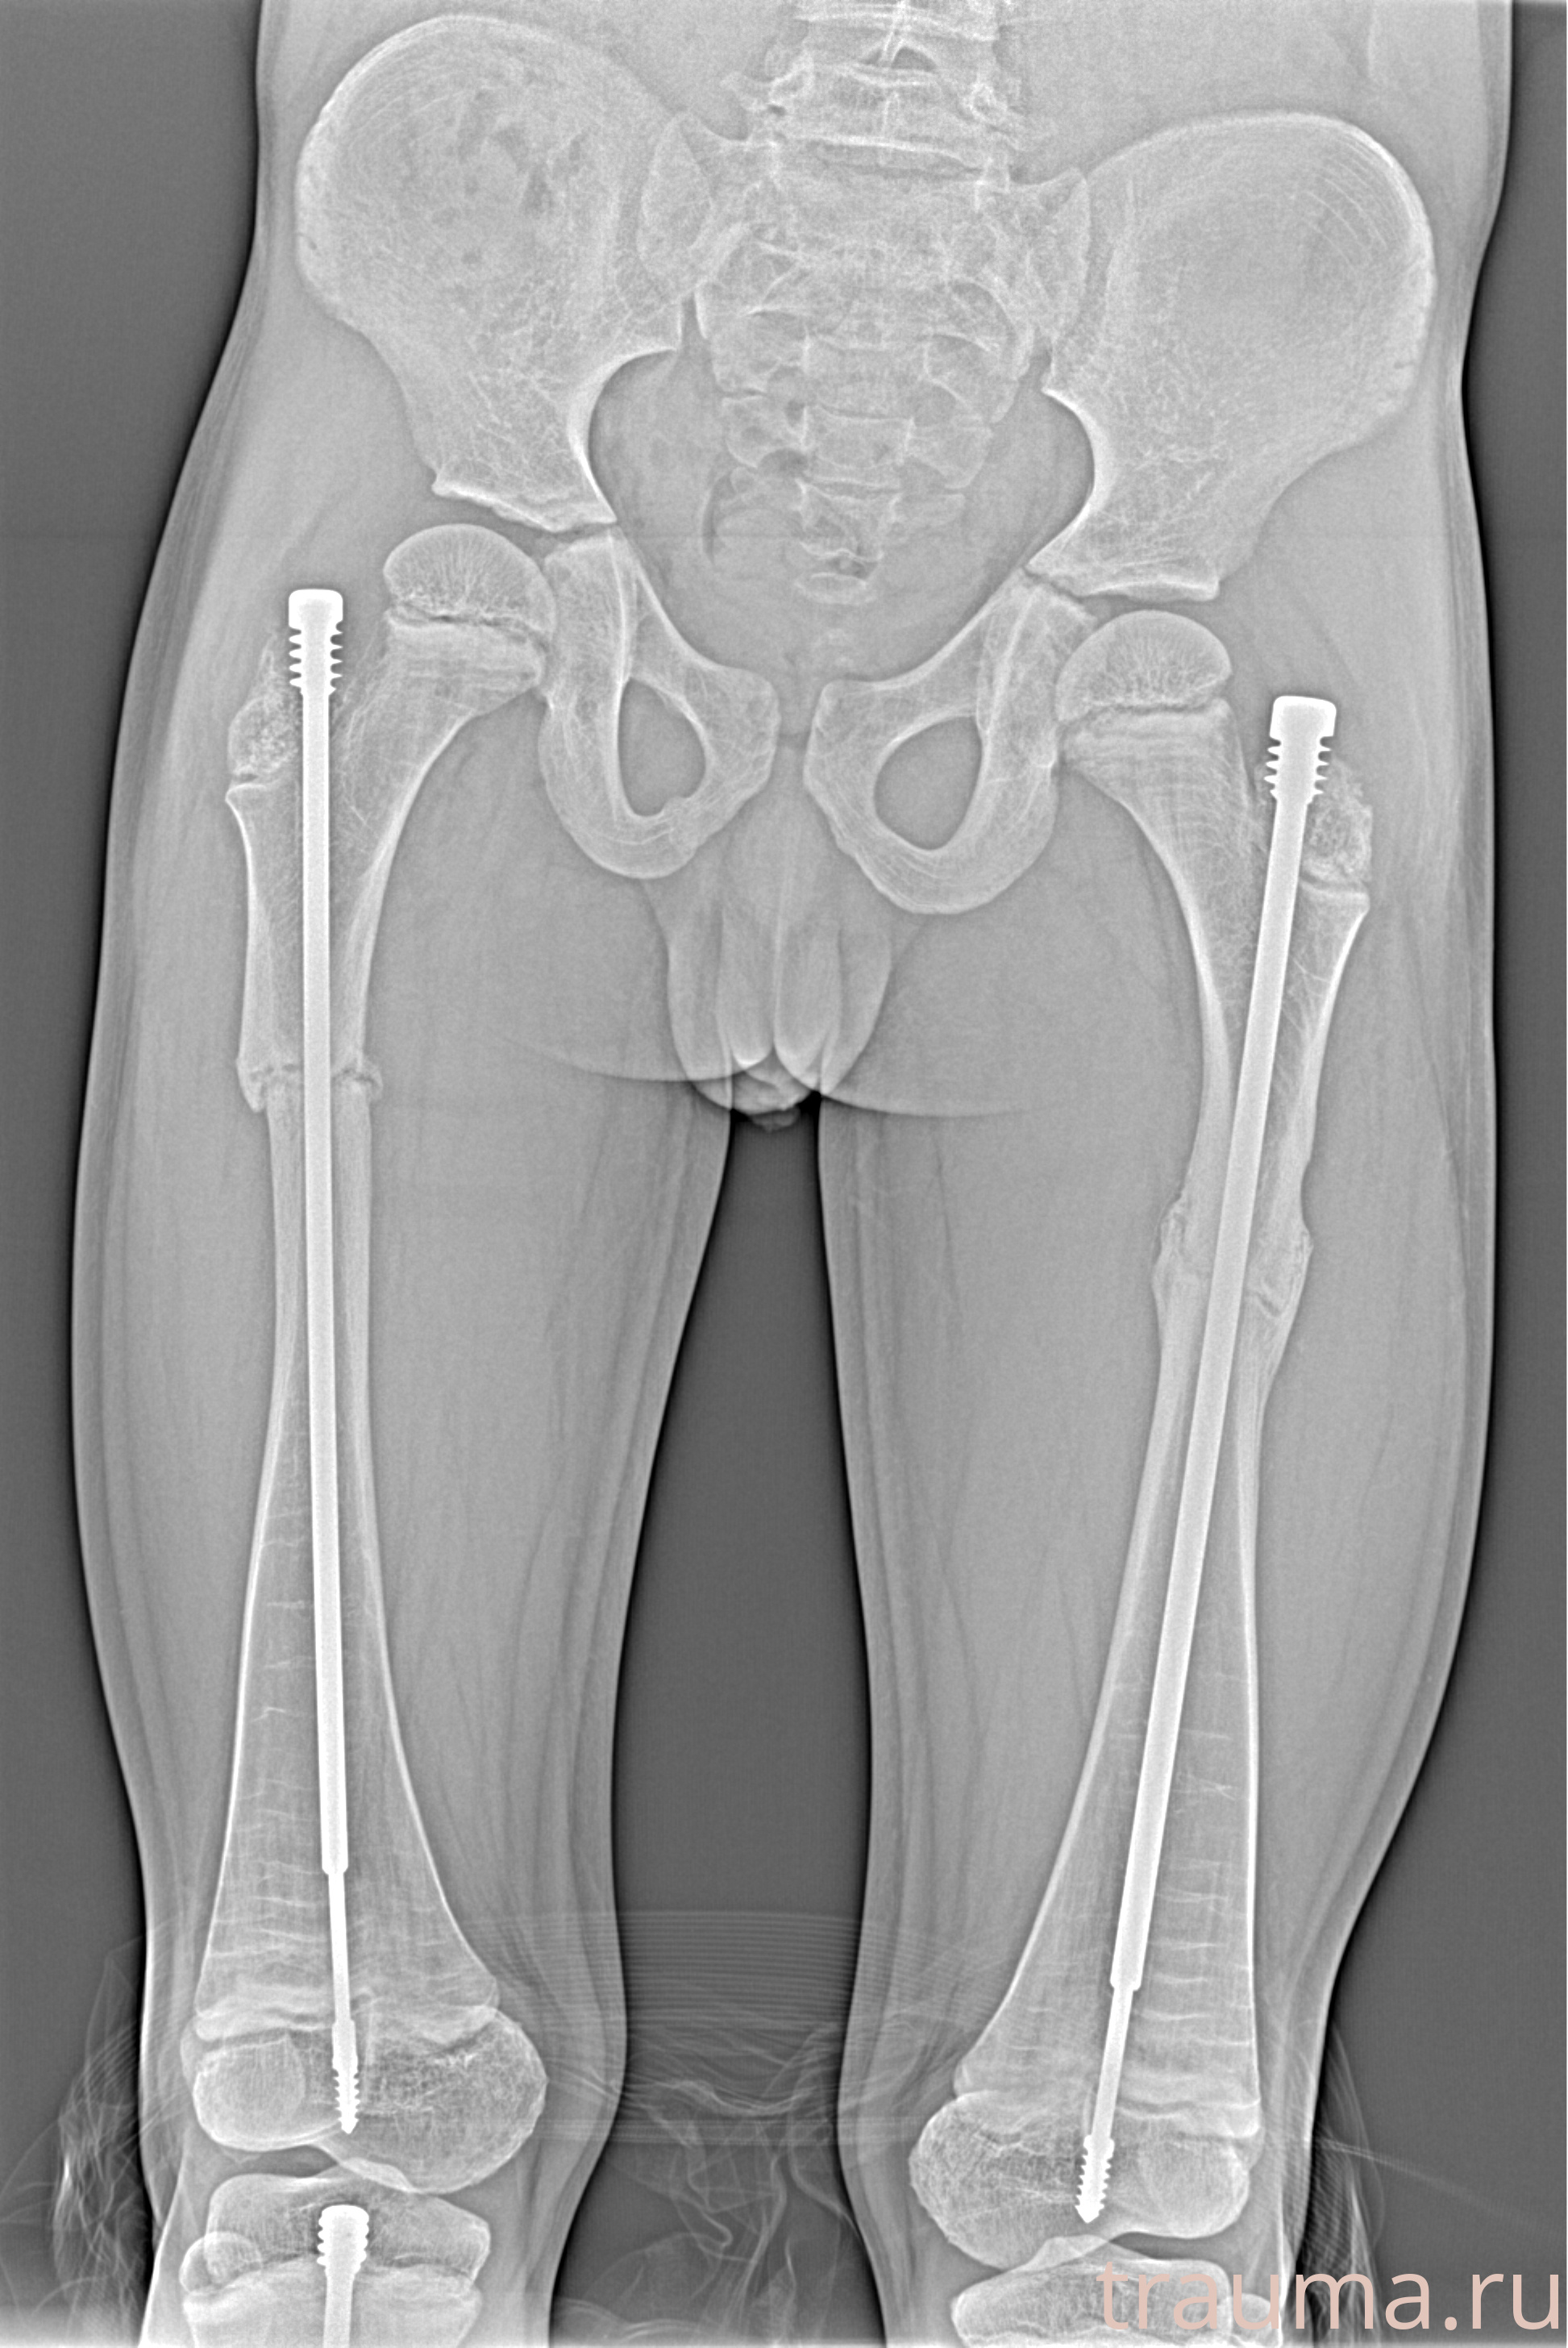

Рентгенограммы

Рентген на дому: по вашему адресу приезжает врач-рентгенолог, травматолог-ортопед с мобильным рентгеновским аппаратом, проводит диагностику травмы или заболевания, делает необходимые рентгенограммы, дает рекомендации по дальнейшему лечению. Получить качественные снимки в домашних условиях возможно благодаря уникальной методике, разработанной МосРентген Центром для института  Склифосовского